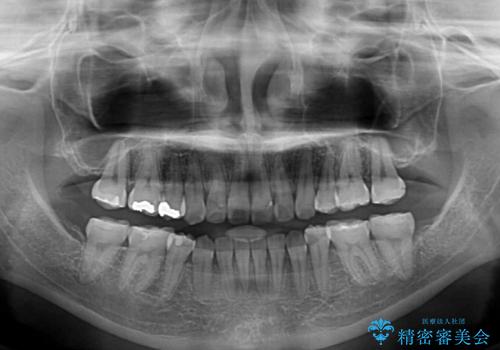

- 上下の八重歯と前歯のデコボコを気にして来院された患者様です。

右上と左下の八重歯が特に著しく、上顎正中が右側にシフトしていました。

デコボコが強いため小臼歯4本を抜歯し、上顎正中を左側に移動させるために補助装置を使用して、ワイヤー装置にて矯正治療を行うこととしました。

八重歯のためずれていた上下の正中をほぼ一致する位置に整えることができました。

重なって汚れの溜まりやすかった部分も改善され、大変満足していただけました。